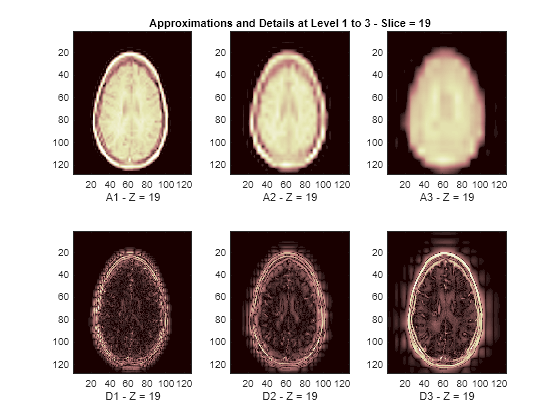

Display Lowpass and Highpass Components

The reconstructed approximations and details along the Z-orientation are displayed below.

nbIMG = 6; idxImages_New = [1 7 10 16 19 25]; for ik = 1:nbIMG j = idxImages_New(ik); figure('DefaultAxesXTick',[],'DefaultAxesYTick',[],... 'DefaultAxesFontSize',8,'Color','w') colormap(map) for k = 1:n labstr = [int2str(k) ' - Z = ' int2str(j)]; subplot(2,n,k) image(A{k}(:,:,j)) xlabel(['A' labstr]) if k==2 title(['Approximations and Details at Level 1 to 3 - Slice = ' num2str(j)]) end subplot(2,n,k+n) imagesc(abs(D{k}(:,:,j))) xlabel(['D' labstr]) end end